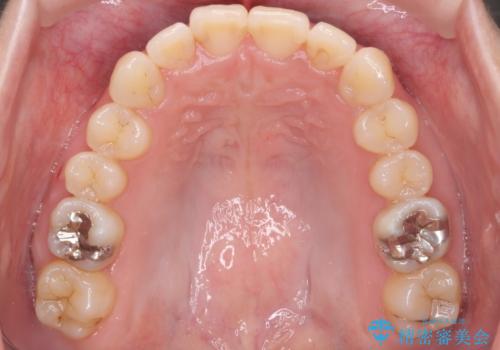

- 前歯のがたつきを主訴に来院。

前歯は目立つのでワイヤー矯正は絶対にしたくないとのことでした。

右上の奥歯を後ろに送り、前歯が出っ歯にならないように並べました。

また、右下の奥歯に一部目立たないように部分的なワイヤー矯正を行い、右下の奥歯が反対咬合になっていたのもしっかり中に入れて治療しています。

奥歯の反対咬合を治すのはインビザラインではかなり難しいのですが、しっかり治療できました。